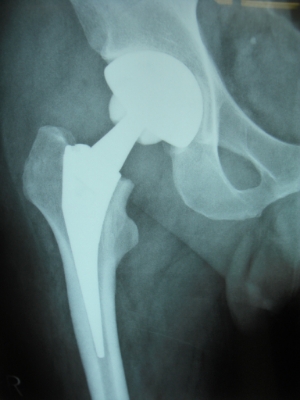

50歳 変形性股関節症 MIS-DAによる人工股関節置換術

術後3日目に歩行訓練開始し術後2週で杖なし歩行で退院